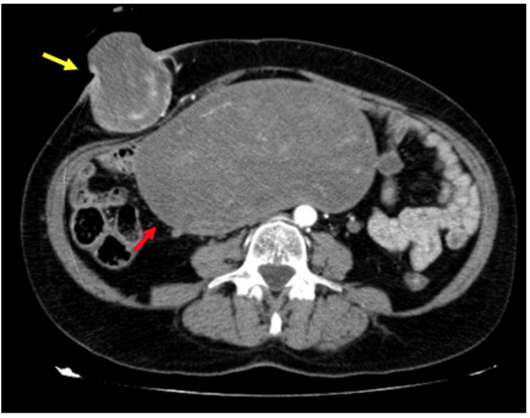

Paciente mujer de 59 años, sin antecedentes médico-quirúrgicos de interés, que consulta al servicio de Urgencias por lesión cutánea ulcerada, de crecimiento progresivo, en fosa ilíaca derecha. Se realizó ecografía abdominal y posteriormente tomografía computarizada (TC) abdominopélvica donde se identificó una masa uterina sugestiva de mioma gigante (180x86x177 mm), muy probablemente malignizado a sarcoma, y una masa subcutánea, sugestiva de metástasis parietal, sin signos de sangrado activo, y sin otros signos de diseminación a distancia (Figura 1). Ante estos hallazgos se decidió llevar a intervención quirúrgica urgente, realizándose resección en bloque de la lesión subcutánea de fosa ilíaca derecha (Figura 2). El estudio anatomopatológico diagnosticó una metástasis de sarcoma del estroma endometrial de alto grado. Se remitió al Comité de Tumores Ginecológicos para completar tratamiento con histerectomía + doble anexectomía + citología de líquido peritoneal en forma programada, por el Servicio de Ginecología y Obstetricia. La paciente recibió tratamiento adyuvante (quimioterapia y radioterapia) con respuesta completa y supervivencia libre de enfermedad en el seguimiento hasta la fecha.

Figura 1. Tomografía computarizada abdominal que muestra tumoración uterina (flecha roja) y metástasis parietal (flecha amarilla).